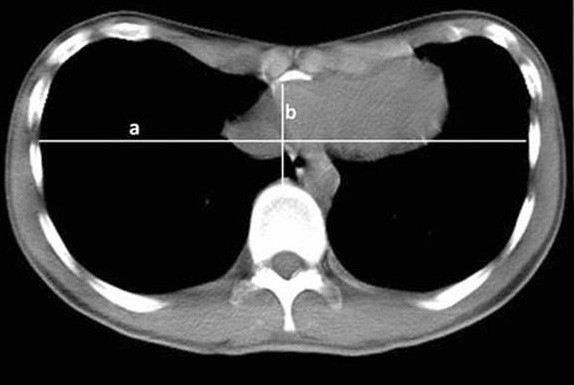

С помощью КТ можно получить информацию о степени искривления и отклонений в структуре хрящей и костных элементов грудной клетки. В отличие от рентгенографии, КТ позволяет более точно определить глубину воронкообразной деформации и её влияние на внутренние органы. Такое обследование включает в себя серию срезов, что даёт полное представление о состоянии грудной клетки и помогает оценить сложность возможных осложнений.

Кроме того, КТ позволяет специалистам определить, как заболевание влияет на симметрию грудной клетки. Эта информация может быть решающей при принятии решения о необходимости хирургической операции или других вмешательств. Важно, что КТ идеально подходит для пациентов, у которых имеются дополнительные заболевания, такие как остеопороз, что может усложнить лечение. Для таких пациентов компьютерная томография помогает выявить возможные риски и избежать ошибок в диагностике.

Процедура начинается с получения стандартного рентгеновского снимка, на котором четко видны изменения в костных и мягких тканях грудной клетки. Для измерения глубины деформации специалисты используют определенные ориентиры, например, расстояние между передней поверхностью грудной клетки и внутренними органами, а также угол искривления ребер. Это позволяет точно установить степень отклонения и классифицировать его по шкале, принятой в медицинской практике.

• Определение глубины воронкообразной деформации: на основе снимков измеряется расстояние между позвоночником и центральной точкой грудной клетки в зоне максимальной воронковидной деформации. Также учитываются данные о наличии отклонений в реберных хрящах.

• Оценка симметрии грудной клетки: на снимках специалист обращает внимание на степень асимметрии, так как это может существенно влиять на выбор метода лечения или операции.